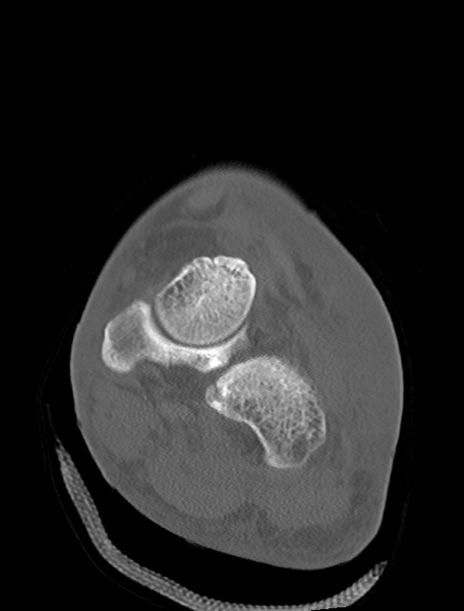

左足関節CT

横断像